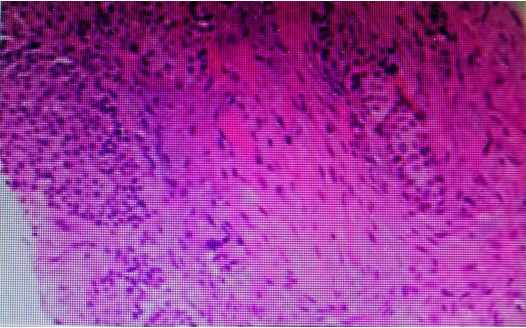

STEP 2:Laparoscopic right kidney ureter bladder partial resection; postoperative pathology indicated: (right renal pelvis) consistent with low-grade papillary urothelial carcinoma, invading the renal parenchyma, with no cancer tissue found at the ureter stump, part of the bladder, renal vascular, or perirenal fat.

Sent for examination (right renal hilar lymph nodes) showed no metastatic cancer. Pathological staging: pT3N0.

Immunohistochemistry: p63(+), CK7(+), P40 (focal +), CK20(-), P53 (scattered +), GATA3 (weak +), HER-2 (2+), Ki-67 (+, about 30%).

Postoperative pathology indicated: infiltrative cancer found in fibrous tissue, supported by medical history and immunohistochemistry results for infiltrative urothelial carcinoma.

Immunohistochemistry results: CK20(-), CK5/6(+), CK7(+), GATA3(+), p16(-), p53 (wild-type expression), p63(+), Pax-8 (focal +), TTF-1(-), Uroplakin III(-), Ki-67 proliferation index approximately 25%, HER2(1+).